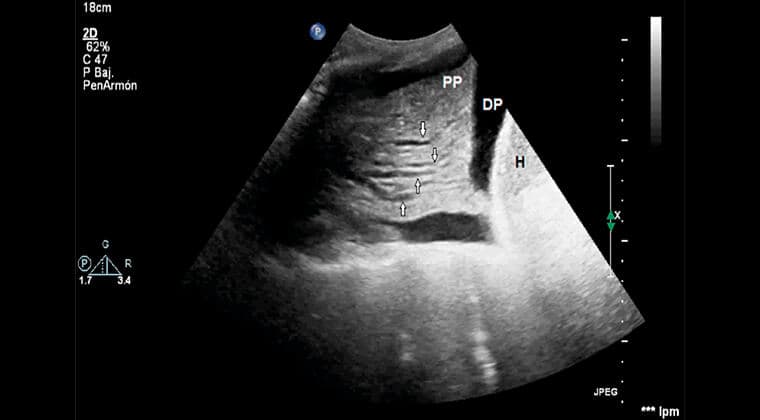

Técnica de imagen no invasiva que evalúa patologías pulmonares y pleurales en tiempo real. Ideal para diagnosticar derrames pleurales, neumonías o edema pulmonar sin radiación.

- Detecta líquido, consolidaciones o colapso pulmonar

Diagnosticar neumonía o derrame pleural y guiar punciones pleurales.